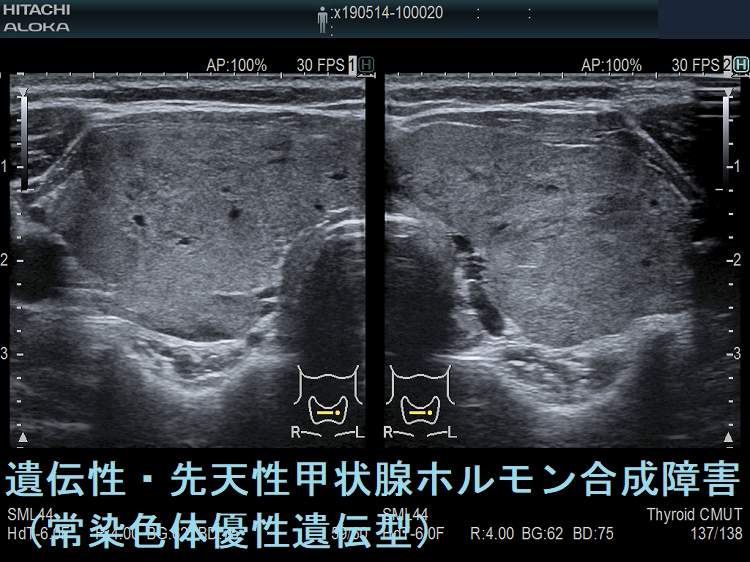

遺伝性甲状腺ホルモン合成障害で、サイログロブリン異常症(サイログロブリン遺伝子異常症)以外は、血中サイログロブリンが上昇するにも関わらず、甲状腺自体の破壊性変化に乏しく、マシュマロ様の軟らかい腺腫様甲状腺腫の形態を取る事があります。

ケース⑦

遺伝性甲状腺ホルモン合成障害に橋本病(慢性甲状腺炎)を合併

遺伝性甲状腺ホルモン合成障害に、橋本病(慢性甲状腺炎)を合併する事があります(橋本病も約70%は遺伝性です)。

遺伝性甲状腺ホルモン合成障害の超音波(エコー)画像は色々なパターンがあります。

- 常染色体優性遺伝型;腺腫様甲状腺腫の形態になります。

- 常染色体劣性遺伝型;新生児マススクリーニングで見つかり、適切に治療された場合、甲状腺サイズは正常、内部は低エコーで、甲状腺ホルモンをほとんど作っていないのが分かります。

橋本病(慢性甲状腺炎)に遺伝性甲状腺ホルモン合成障害の軽症例を合併

橋本病(慢性甲状腺炎)を合併すると、遺伝性甲状腺ホルモン合成障害の軽症例がマスクされ、あたかも甲状腺機能正常橋本病による腺腫様甲状腺腫のように見えます(橋本病も約70%遺伝です)。